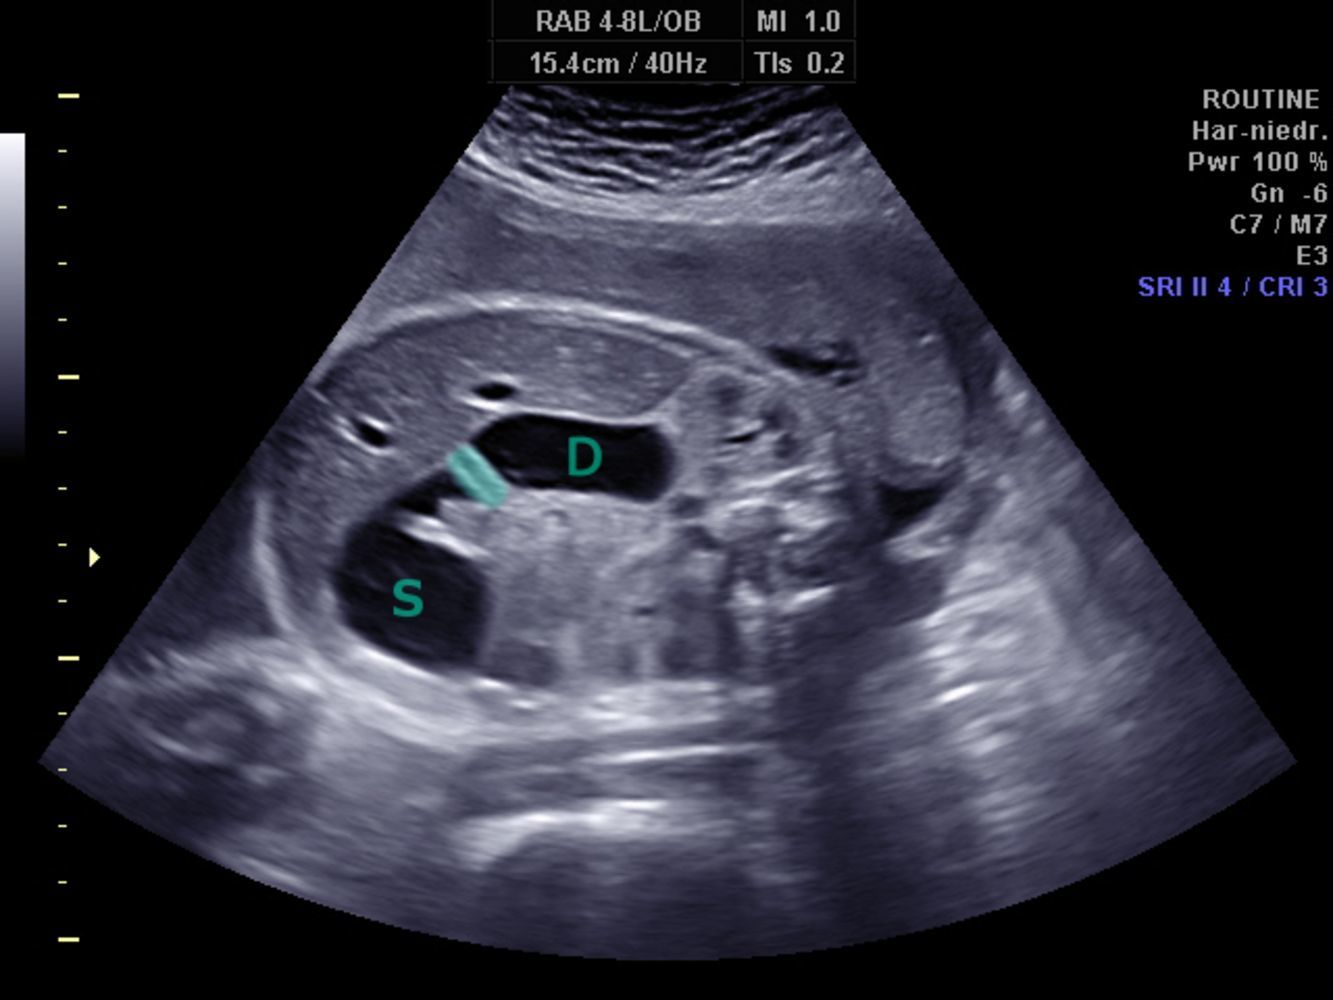

Double Bubble Sign on Ultrasound Seen in Duodenal Atresia

S → stomach

D → proximal duodenum

Shaded area → pyloric sphincter

(dilation of the pre-stenotic bowel segments (duodenum (D) and stomach (S)) with an air-fluid level in each dilated segment (double bubble sign). No air is visible in the post-stenotic bowel loops)